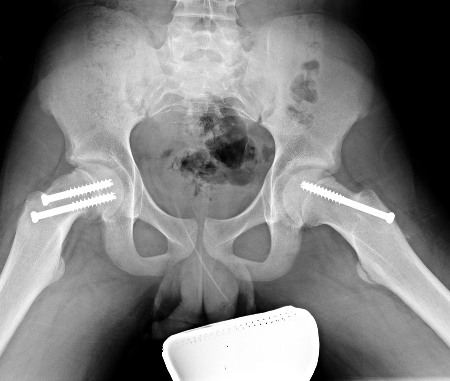

O tratamento da EPF instável é semelhante ao da EPF estável. No entanto, há diferenças quanto ao momento da cirurgia, à descompressão da articulação do quadril, à redução incidental da EPF e ao método de estabilização com 1 ou 2 parafusos.[Figure caption and citation for the preceding image starts]: Epifisiólise proximal do fêmur (EPF) instável no quadril direito fixo com 2 parafusos. Fixação profilática do quadril esquerdo com um único parafuso. Radiografia pós-operatória anteroposteriorImagem cedida por John M. Flynn, MD [Citation ends].

O parafuso é colocado no centro da epífise nas regiões anteroposterior e lateral.[Figure caption and citation for the preceding image starts]: Epifisiólise proximal do fêmur (EPF) instável no quadril direito fixo com 2 parafusos. Fixação profilática do quadril esquerdo com um único parafuso. Radiografia pós-operatória anteroposteriorImagem cedida por John M. Flynn, MD [Citation ends].